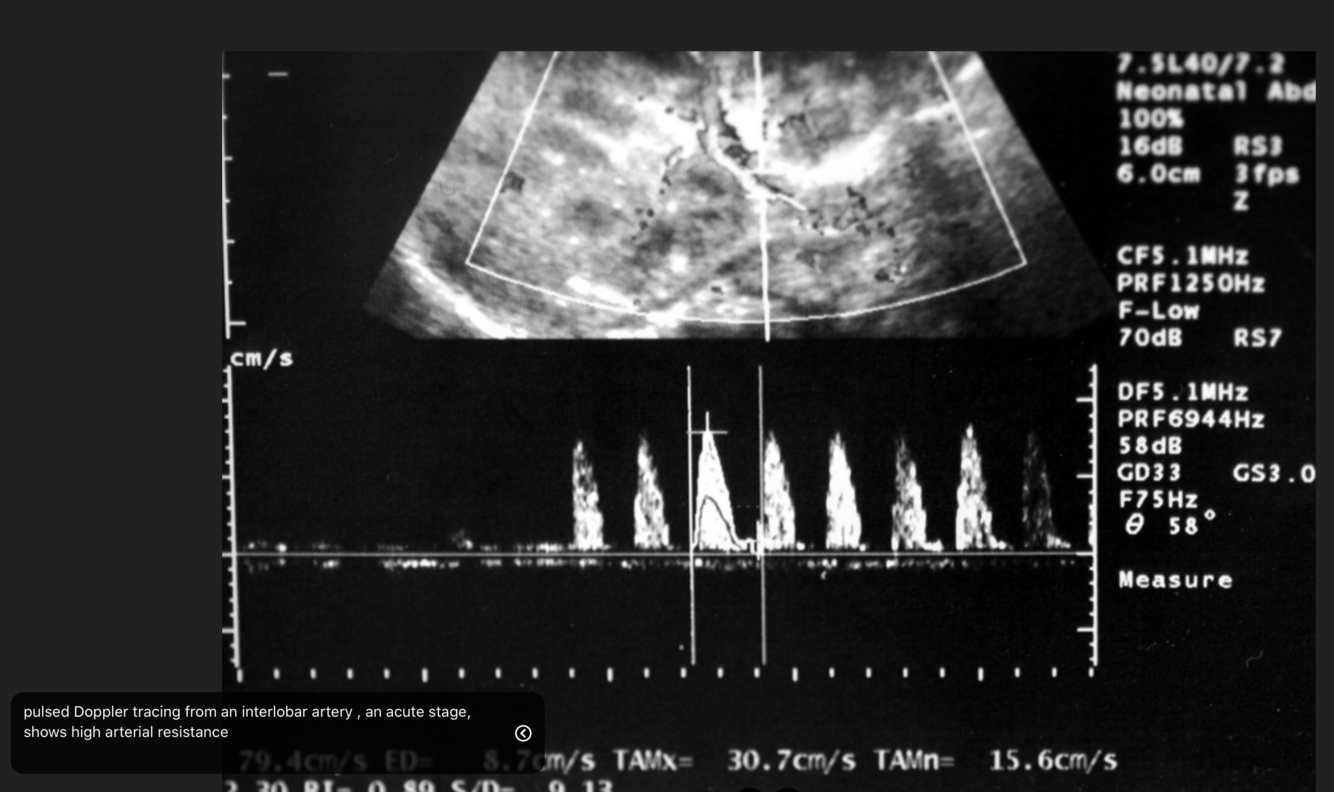

What are the signs of renal vein thrombosis in the kidneys on USS?

Early and late phases

Kidneys